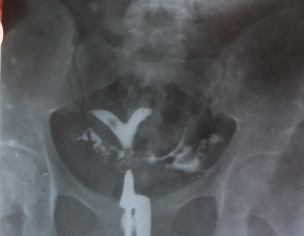

Assalam u alaikum. I have been trying to conceive since last 1 married before 2 years. I tried to visit many gynecologist. And they treated differently, recently I visited a professor gynecologist, she has done many tests and HSG, Hysterio salpingo gram XRAYS, finally she prescribed surgery. Doctor told that both tubes are patent . So I wanted to know that what's our problem and what's its treatment ? Is blocked tubes can be treated without surgery ? Is there any risk of surgery ? I have also attached all the tests ,and xray reports. Also I have attached semen analysis test. Please admin tag the best gynecologist. I'm waiting for response. Thanks

waa. both tubes are patent. bicornuate uterus does not prevent conception, it may result in pregnancy complications. surgery will help prevent complications. but for conception other causes are to be ruled out n treatment done. u may discuss with me properly through Marham online visit. Allah bless you. tc

Salam . After seeing ur reports there is no problem in any one of u . Ur husbands semen analysis is fine . . Ur tests r fine . Ur HSG shows ur tubes r fine there is no blockage except the uterus is a bicornuate uterus meaning it is a heart shaped uterus which is congenital that is by birth . There is no problem in conceiving with bicornuate uterus . Also this is not confirmatory on HSG that the uterus is heart shaped . This is confirmed by TVS ultrasound pelvis or MRI pelvis . But it doesn’t hinder or give problem in conceiving . Surgery is done to correct it but not required everytime . U can conceive without surgery as well . Thanks

ur tubes r patent only bicornuate uterus that cause pregnancy complication not problem in conception... semen also normal ranges only few WBC n 1-2 RBC means mild infection that can b treated with antibiotics so refer him to urologist like Dr. Amjad noor